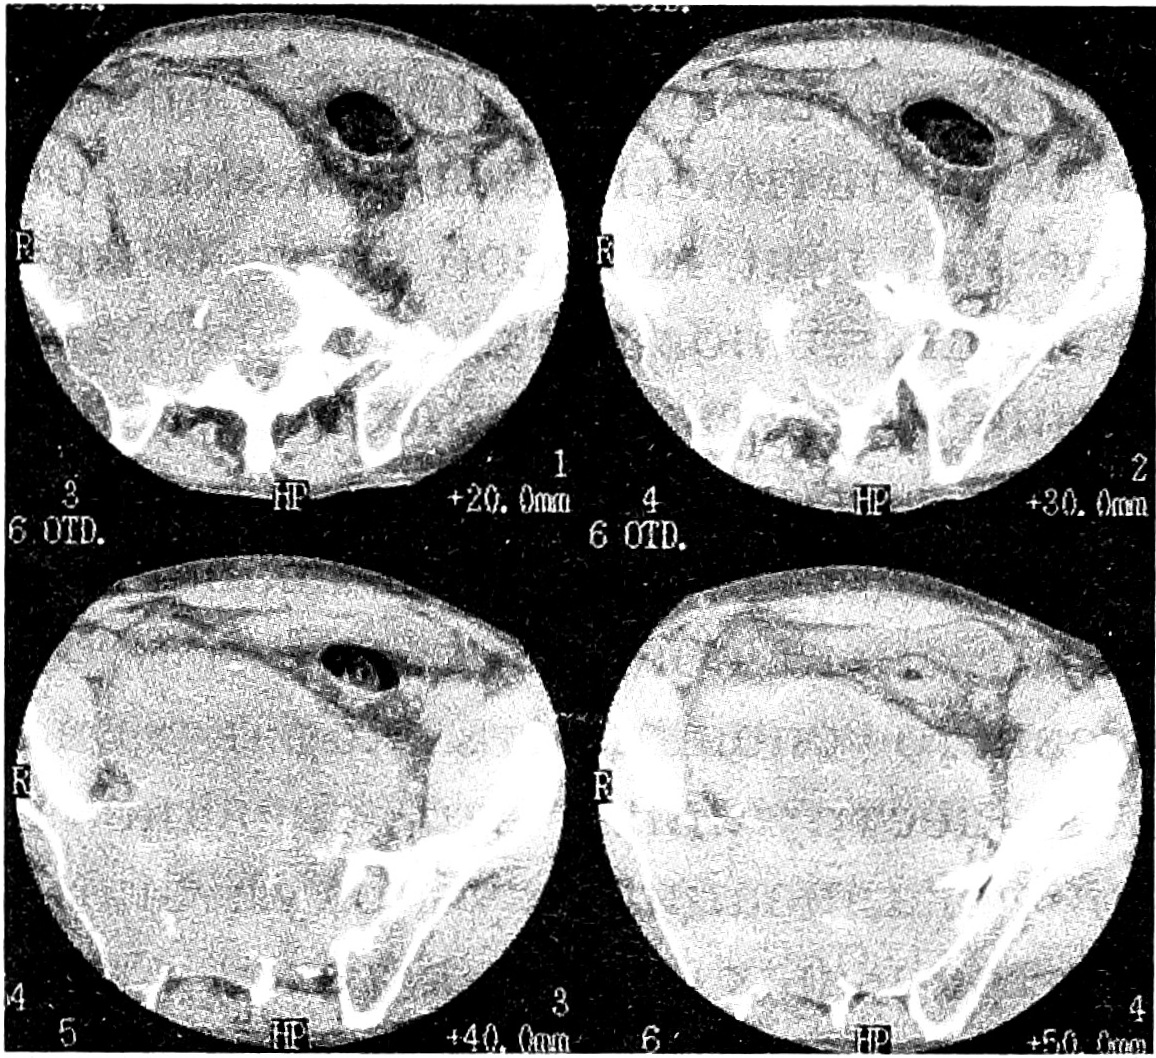

Рис. 4. Больной М., 34 лет. Диагноз: неврилеммома S3-S5, рецидив, озлокачествление.

a — аксиальная КТ: остеолитический очаг деструкции S3-S5, экстравертебральный компонент опухоли, грубые обызвествления и костеобразование; б — Т1 взвешенные МРТ в сагиттальной проекции: изоинтенсивный гетерогенный сигнал от опухоли в форме «песочных часов», гипоинтенсивный сигнал от капсулы; в — Т2 взвешенные МРТ в сагиттальной проекции: гиперинтенсивный сигнал от опухоли.